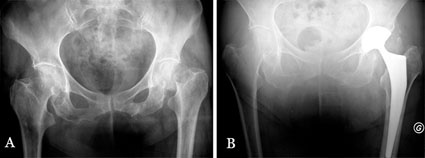

Die in dieser Studie implantierte tripolare Pfanne besteht aus einer M30NW-Stahlaußenschale mit hochpolierter Innenseite für das darin gleitende bipolare UHMW PE-Inlay vom Typ SATURNE der Firma Amplitude (Abb. 4). Der Femurkopf wird mittels Verpressung intraoperativ im Inlay verankert und gemeinsam mit diesem auf das Femurschaftimplantat impaktiert. Die Pfannenaußenschale wurde in 165 Hüften zementfrei (mit Titanplasma- und Hydroxylapatit-Beschichtung) implantiert und in 2 Fällen unter Verwendung einer Pfannendachverstärkung zementiert implantiert. In 157 Hüften (94%) wurde ein Femurschaftimplantat mit einheitlichem Design verwendet. Die HA-beschichtete Ausführung, Typ INTEGRALE der Firma Amplitude, wurde in 147 Fällen zementfrei implantiert (Abb. 5 und 6), in 10 Fällen wurde die zementierte Ausführung, Typ GENERIC, verwendet. In den übrigen 10 Fällen war eine endoprothetische Rekonstruktion des proximalen Femurs mit einem Rekonstruktionsschaft erforderlich.

Keine Dislokationen

Zum Zeitpunkt des letzten Follow-Ups wurde keine Luxation festgestellt und kein Patient hatte die Erfahrung einer Subluxation gemacht. Der mittlere präoperative Harris-Hip-Score verbesserte sich von 39,6 (11-100) auf 83,4 (25-100) zum Zeitpunkt des letzten Follow-Ups (P <0,05). Keine Fehlpositionierung des Pfannenimplantats (definiert als 10° Abweichung gegenüber dem optimalen Pfannensitz bei 45° Inklination) wurde in der Koronarebene festgestellt. Ein zementfreies Pfannenimplantat zeigte Migaration 8 Tage postoperativ, bei einer 72 Jahre alten Patientin mit einer traumatischen azetabulären Diskontinuität, die zum Zeitpunkt der Operation nicht fixiert war. Die Behandlung bestand aus einer Revision mit interner Fixierung und Einsatz einer Pfannendachschale mit einem zementierten tripolaren Implantat. Es gab keine weitere Pfannenmigration.

Zur Reduktion des Dislokationsrisikos wurde daher eine tripolare Pfanne zur primären Hüft TEP Versorgung ausgewählt, um die Stabilität zu erhöhen. Das Implantat war sehr erfolgreich, keine einzige Dislokation trat im Beobachtungszeitraum auf, die Funktionalität verbesserte sich erheblich.